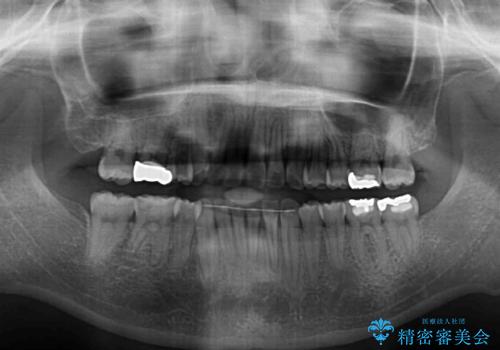

- 上下の八重歯を気にして来院された患者様です。

上下ともに八重歯の後ろの歯を1歯ずつ抜歯し、補助装置(リンガルアーチ)を用いて八重歯の位置を改善し、その後インビザラインにより矯正治療を行うこととしました。